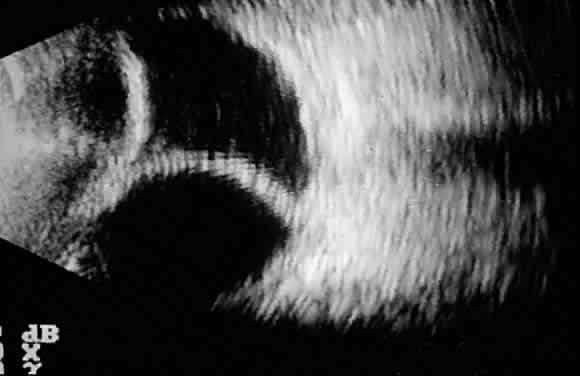

INTRAOPERATIVE AND POSTOPERATIVE SUPRACHOROIDAL HEMORRHAGE Suprachoroidal hemorrhage is a serious complication that can be seen during or after any intraocular surgery. If it occurs intraoperatively and cannot be controlled (i.e., expulsive hemorrhage), it can lead to loss of vision. The incidence of this complication in the general population after cataract extraction is approximately 0.2%.1–3 The incidence of suprachoroidal hemorrhage in glaucoma patients undergoing various types of intraocular surgery has been reported to be 0.73%.4–6 Ocular risk factors for suprachoroidal hemorrhage include glaucoma, aphakia, pseudophakia, previous vitrectomy, vitrectomy at the time of glaucoma surgery, myopia, and postoperative hypotony. Systemic risk factors are arteriosclerosis, high blood pressure, tachycardia, and bleeding disorders. The source of the hemorrhage usually is one of the posterior ciliary arteries, particularly the point of entrance of the short posterior ciliary vessels into the suprachoroidal space. There seems to be a vascular necrosis and subsequent rupture of the vascular wall.7 Intraoperative suprachoroidal hemorrhage can be associated with sudden collapse of the anterior chamber. The patient may complain of sudden pain breaking through the local anesthesia. If the process is gradual, a dark mass can be observed through the pupil to evolve slowly, but if the process is abrupt the hemorrhage is more expulsive. Postoperative suprachoroidal hemorrhage usually occurs within the first week after glaucoma surgery and usually is associated with postoperative hypotony4–6 (Fig. 1). The development of a suprachoroidal hemorrhage typically is acute and associated with the sudden onset of severe pain. Examination of the anterior segment frequently reveals a shallow anterior chamber and a normal or high intraocular pressure (IOP). On fundus examination, a detached and dark choroid is noted. The choroidal elevations have a dark, reddish brown color. Some patients present with bleeding into the vitreous cavity and, uncommonly, retinal detachment. Ultrasonography can be used to diagnose suprachoroidal hemorrhage when fundus examination is not possible. Intraoperatively, once a suprachoroidal hemorrhage has been identified, prompt and secure closure of the incision is the first goal of the treatment, with gentle repositioning of prolapsed uvea. The surgeon's finger can be used to tamponade the incision site temporarily while sutures are placed. Meanwhile, intravenous acetazolamide (500 mg) and mannitol 20% (1 to 1.5 g/kg) are administered. Once the eye has been closed, the anterior chamber can be reformed through the incision or a paracentesis tract. After this point, a conservative approach probably is appropriate. Some authors advise immediate drainage of the hemorrhage through posterior sclerostomies (usually not possible because it rapidly clots), sometimes combined with a vitrectomy in aphakic patients, especially if the hemorrhage is large. Prognosis for recovery of vision is good as long as the eye can be closed without loss of uvea. Treatment of postoperative suprachoroidal hemorrhage is directed toward control of the IOP and relief of pain. Most of these eyes do well with this conservative management, and surgical drainage usually is not necessary.8 The indications for drainage include intolerable pain, a persistent flat anterior chamber, and massive “kissing” choroidal detachments (see later). A waiting period of about 7 days after a suprachoroidal hemorrhage is advised for the fibrinolytic response to liquefy the clot and allow for more effective evacuation of the suprachoroidal space. Drainage through a sclerotomy into the suprachoroidal space reveals liquefied blood, which usually is red or black. Occasionally, the fluid drained is a mixture of clear, straw-colored fluid and reddish to black liquefied blood. Bleeding into the vitreous cavity at the time of the hemorrhage and retinal detachment worsen the visual prognosis. Prevention Several steps can be taken in high-risk eyes. Before surgery, correction of bleeding problems and discontinuation of inhibitors of platelet aggregation (i.e., acetylsalicylic acid) is recommended. Preoperative intravenous mannitol at the time of surgery should be used. Prophylactic sclerostomies can be helpful. Use of viscoelastic and tight suturing of the scleral flap to prevent hypotony are recommended. The patient is urged to restrict activities (bending, weight lifting) and to avoid Valsalvapositive conditions (constipation, vigorous coughing, sneezing, or nose-blowing) during the early postoperative period. HYPHEMA Hyphema is a common postoperative occurrence in glaucomatous eyes after filtration surgery, surgical peripheral iridectomy, and trabeculotomy. Bleeding commonly arises from the ciliary body or cut ends of the Schlemm's canal, although it also might arise from the corneoscleral incision or iris. In general, hyphema presents at surgery or within the first 2 or 3 days after surgery. Intraoperatively, if a bleeding spot does not stop spontaneously, it must be identified and coagulated. During filtration surgery, bleeding is decreased by performing the internal sclerostomy as far anteriorly as possible. In most cases, no treatment is necessary and the blood is absorbed within a brief period of time. Cycloplegics, corticosteroids, restriction of activity, and elevation of head of the bed 30° to 45° (to prevent blood from obstructing a superior sclerostomy) are recommended. Increased IOP can occur, particularly if the filtering site is obstructed by a blood clot, and it should be treated if necessary with aqueous suppressants. Injection of tissue-plasminogen activator may be considered (see later). Surgical evacuation is considered depending on the level of IOP, size of hyphema, severity of optic nerve damage, likelihood of corneal blood staining, and presence of sickle trait or sickle cell anemia (infarction of the optic nerve can occur at relatively low IOP, and carbonic anhydrase inhibitors are contraindicated). Liquid blood can be easily removed with irrigation. If a clot has formed, it can be removed by expression with viscoelastic or with a vitrectomy instrument set at low vacuum. HYPOTONY Hypotony (i.e., IOP less than 6 mmHg) after glaucoma surgery can result from excessive aqueous outflow (related to excessive filtration [see later], wound leak, or cyclodialysis cleft) or to reduced aqueous production (related to ciliochoroidal detachment, inflammation, inadvertent use of aqueous suppressants, or extensive cyclodestruction).9 These conditions can coexist. For example, low IOP from overfiltration can induce ciliochoroidal detachment and secondary decreased aqueous production. Possible complications include flat anterior chamber, gradual failure of the bleb, visual loss, cataract, corneal edema, Descemet's membrane folds, choroidal hemorrhage, macular and optic disc edema, and chorioretinal folds (predominantly in young myopic patients). According to Spaeth (Table 1),10 the severity of flat anterior chamber can be classified as grade I when there is peripheral-iris apposition, grade II with pupillary border-corneal apposition, or grade III with lens-corneal touch (see Chapter 15). The central anterior chamber depth also can be described relative to the corneal thickness. Choroidal effusion occurs when fluid collects in the suprachoroidal space (Fig. 2), resulting in forward movement of the lens iris diaphragm with anterior chamber shallowing. On fundus examination, moundlike elevations of the choroid, more commonly in the periphery, are visible.